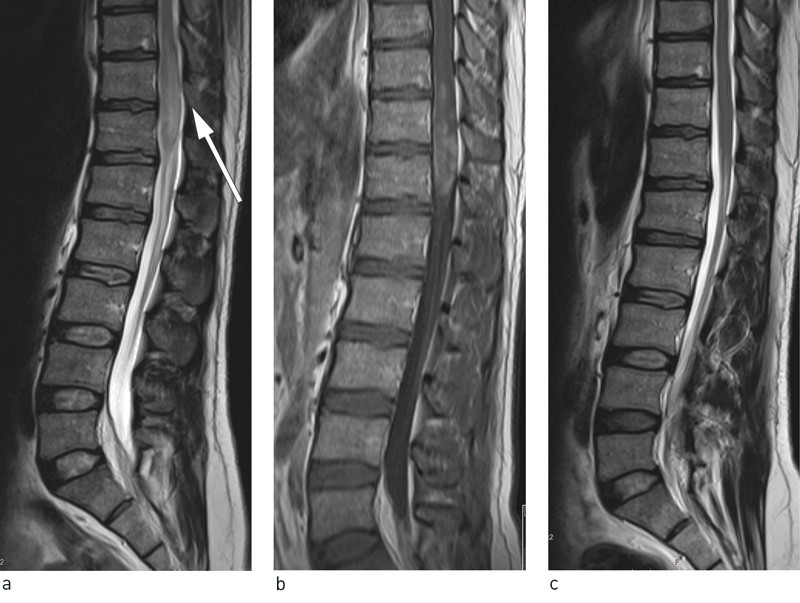

MR-bilder av columna viste en patologisk intramedullær lesjon i nivå Th10/Th12 (fig 1a, b). I distale medulla fant man en 6 cm lang, spindelformet oppdriving som strakte seg til konus. Lesjonen hadde et inhomogent signal, høyere enn medulla på T2. Etter kontrast var det flekkvis, inhomogen kontrastoppladning. Medulla var såpass oppdreven at den fylte det meste av spinalkanalen.

Funnet var ikke typisk for solid tumor, transvers myelitt eller demyeliniserende sykdom, selv om det ikke kunne utelukkes. Ut fra bildefunn og klinisk undersøkelse antok man at infeksiøs årsak var en høyst aktuell differensialdiagnose, og beskrivende radiolog bemerket at schistosomiasis kunne ha et svært likt utseende. Tuberkulose var mindre sannsynlig på grunn av lokalisasjon og utseende av lesjonen og at isolert affeksjon av medulla er svært sjeldent.

Ved undersøkelse ett år etter utskrivning hadde han fremdeles smerter i høyre side av korsryggen, men smertene var mindre uttalte enn før behandlingen for schistosomiasis. Pasienten sa at han de første tre månedene hadde hatt problemer med vannlatingen, men det hadde gradvis normalisert seg. Han hadde ingen pareser. Han anga lett nedsatt berøringssans på høyre underekstremitet og lett nedsatt vibrasjonssans. Mannen var i arbeidstrening og ønsket å komme tilbake i arbeid. Ny MR-undersøkelse viste fullstendig regresjon av tidligere påviste funn (fig 1c).

Vurdering av schistosomiasisinfeksjon i hepatospleniske og urogenitale organer kan gjøres ved bruk av ultralyd, CT- og MR-undersøkelser. Ultralyd kan gjøres på sengepost og i felten og krever betydelig mindre økonomiske investeringer enn de andre modalitetene (8). CT-undersøkelse er spesielt bra for å vise forkalkninger i urinveiene, noe som er typisk for urogenital schistosomiasis (9). For ektopisk form med cerebral affeksjon eller myeloradikulopati er MR-undersøkelse beste metode. Blant befolkningsgruppene som er mest rammet, er imidlertid denne modaliteten sjelden tilgjengelig. Ved nevroschistosomiasis er distale medulla/conus hyppigst affisert. På T2-sekvensen ser man heterogene høysignalforandringer og oppdrivinger av medulla, gjerne over flere segmenter. Det kan være både nodulær kontrastoppladning i medulla og perifer oppladning i leptomeningene på grunn av egg med granulomadanning begge steder. I en del tilfeller er det også affeksjon av nerverøtter og cauda equina (10) – (12).

Undersøkelser av spinalvæsken viser økt proteinkonsentrasjon og antall mononuklære celler hos 90 % av pasientene med slik myeloradikulopati (14). Det var også tilfelle hos vår pasient. MR-diagnostikk har vist seg spesielt verdifullt for denne pasientgruppen og førte også til rett diagnose i vårt tilfelle.

Ved etterundersøkelse ett år etter behandling var MR-funnene i spinalkanalen gått helt tilbake. Det viser at behandling selv lenge etter infeksjonstidspunkt har effekt. Denne observasjonen er viktig fordi svært få personer med nevroschistosomiasis blir etterundersøkt med MR-undersøkelse.